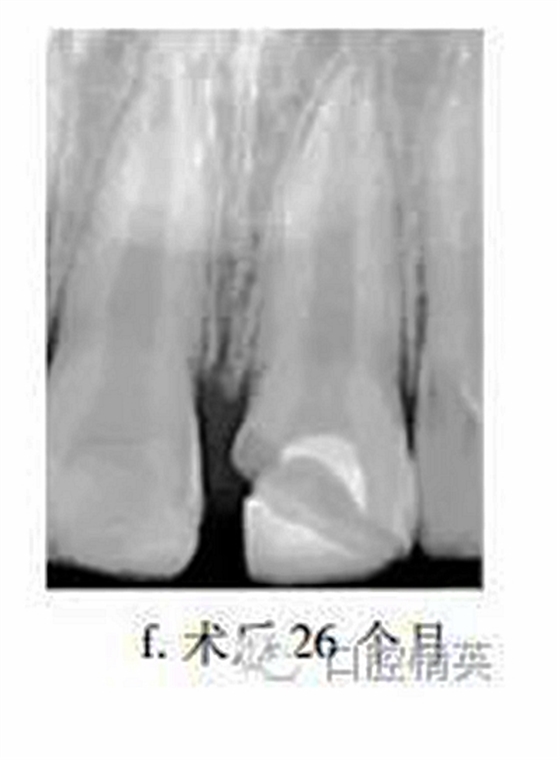

26個(gè)月后復(fù)查,患牙無(wú)不適,牙髓活力測(cè)試較正常牙齒略低,冠部充填物部分脫落,X線片示:患牙蓋髓劑下方可見(jiàn)連續(xù)薄層高密度影像,髓腔縮窄,根尖孔聚攏,牙根長(zhǎng)度較鄰牙無(wú)明顯差異(圖f)?;佳廊コ糠植Aщx子水門汀,備釘?shù)?,隔濕,納米樹(shù)脂修復(fù)冠缺損,調(diào)牙合拋光。

眾多臨床研究表明,MTA用于活髓切斷術(shù)的臨床療效優(yōu)于傳統(tǒng)的蓋髓劑氫氧化鈣,除去MTA較氫氧化鈣具有更好的封閉性以外,低細(xì)胞毒性是其另一重要特點(diǎn)。MTA體外實(shí)驗(yàn)中可促進(jìn)正常牙髓細(xì)胞的牙向分化能力,亦能提高成骨細(xì)胞的體外骨向分化能力。有學(xué)者發(fā)現(xiàn)早期炎癥狀態(tài)下,牙髓干細(xì)胞的體外增殖與成牙能力降低,而成骨能力上調(diào),本病例26個(gè)月復(fù)查X線片中發(fā)現(xiàn)MTA下方有薄層連續(xù)高密度影像,牙根伸長(zhǎng),根尖孔聚攏,提示創(chuàng)傷暴露后的牙髓(干)細(xì)胞在MTA誘導(dǎo)下,具有較強(qiáng)的修復(fù)能力。